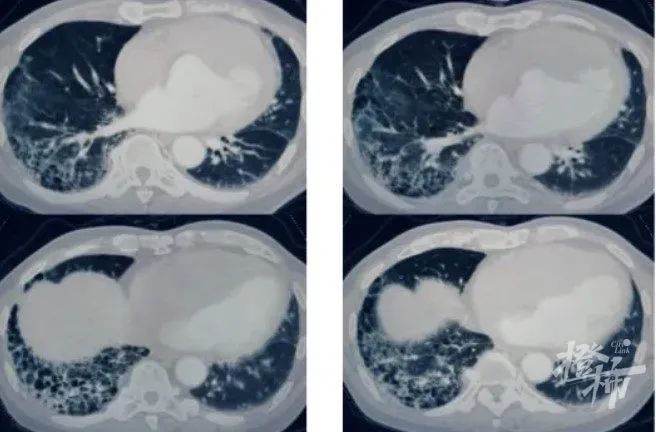

沈凌医生立即为病人安排了肺部CT检查,在查看影像资料时,他惊讶地发现,

王大伯肺部已经出现明显的肺纤维化特征,更为严重的是,局部已经形成了蜂窝状的病变形态。